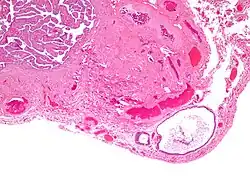

Pathology

It has been suggested that these cell rests are the histogenetic origins of Brenner tumors, due to the histological similarity of the epithelium of Walthard cell rests and Brenner tumors to the urothelium of the lower urinary tract. Also, it has been proposed that Brenner tumors and Walthard cell rests signify urothelial differentiation within the female genital tract.